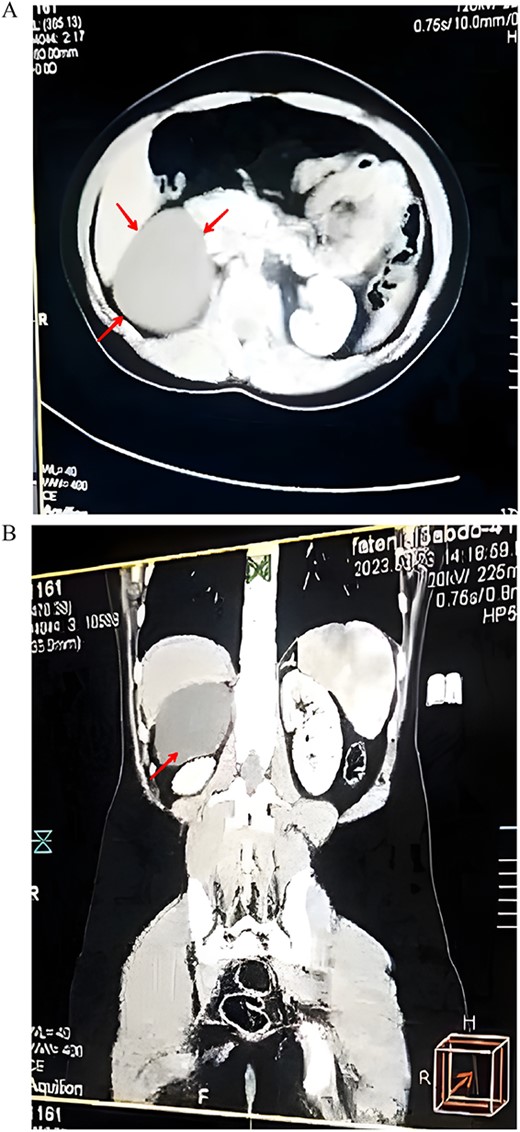

A 17-year-old female presented with mild pain in her right flank for the past 4 months. The pain was non-radiating and not associated with nausea or vomiting. The patient had the same complaint a year ago, which was disregarded because of the lack of access to a healthcare center. The pain did not relieve on medication and the patient was referred to our department. On physical examination, the abdomen was soft and non-tender without distention. There was no dysuria, hematuria, or fever. There was no history of weight loss, loss of appetite, or change in bowel movement. The patient had normal puberty, current menstrual cycle is regular and no hirsutism was observed. Patient’s past medical and surgical history was insignificant. Vital signs and blood tests were within normal. Renal/hepatic function panel was within normal range. Abdominal ultrasound showed a large cystic lesion measuring 9 × 9 × 12 cm on the right kidney (Fig. 1). Subsequent abdominal computerized tomography (CT) with contrast showed a large, well-defined, clear fluid-filled suprarenal cyst posterior to the liver, isolated from the liver, right kidney, and the right adrenal gland measuring 8 cm (Fig. 2A–B). Depending on the imaging results which were mistakenly found consistent with a mesenteric cyst, we opted for laparoscopic surgery since the cyst was symptomatic. A surgical exploration of the abdomen revealed an adrenal cyst. The cyst was excised along with the right adrenal gland. Histopathological examination of the resected cyst showed the cystic wall lined by a single layer of cuboidal or flattened epithelium with other sections of normal adrenal cortex tissue, confirming the diagnosis of an epithelial adrenal cyst (Fig. 3). The patient was discharged the next day, her recovery was uneventful and the pain resolved after the removal of the adrenal cyst and did not require further treatment.

(A) An axial CT scan showing a well-defined suprarenal cyst (arrow). (B) A coronal CT scan of the abdomen showing the location of the cysts in the right upper quadrant (arrow).